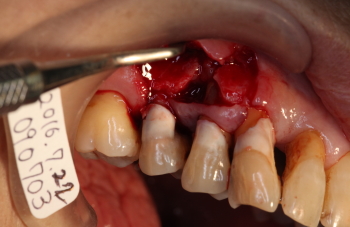

| 2016年07月22日 14番の歯牙の動揺と排膿と痛みとしみ |

| 2016年07月22日 同部を切開、剥離 |